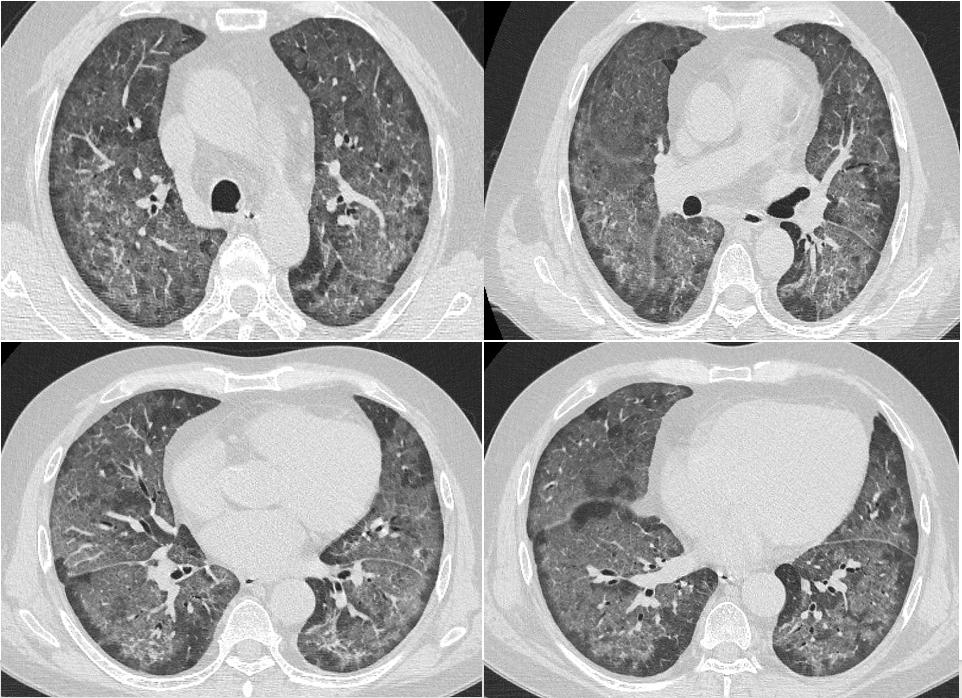

2022年7月17日:患者气喘较前明显好转,改口服SMZ;7月18日:复查胸部CT。患者仍有活动性气喘,暂续前治疗;7月20日:气喘明显加重,急查血气;7月22日:炎症指标上升,转ICU行气管插管+呼吸机辅助呼吸,CRRT。

2022年7月18日,患者胸部CT见双肺间质性炎症范围较前扩大,考虑PJP感染导致的间质性炎症持续渗出。

患者属重症PJP,给予静脉使用SMZ注射液病情一度好转,但因经济原因,改为口服SMZ治疗,后病情进展迅速。

2022年7月24日,BALF-mNGS检出耶氏肺孢子菌、肺炎克雷伯菌。肺炎克雷伯菌系院内感染。7月28日,多次复查血常规提示血小板进行性下降;8月8日:抗生素降阶梯;8月10日:气管插管2周,暂难脱机,需行气管切开,血小板低,输注血小板,择期行气切;8月13日:血小板进行性下降,感染消耗可能。血小板27X109/L、CRP89.2mg/L;8月16日:复查血常规示三系进行性下降,降钙素原升高15.6ng/ml,感染加重;8月17日:炎症指标较前明显升高,调整抗生素。血小板16X109/L、CRP272mg/L;8月18日:患者深昏迷,FIO2100%,血氧饱和度波动于60%-80%,去甲肾上腺维持血压,随时可能出现死亡风险,患者家属强烈要求出院,劝阻无效,予办理自动出院。血小板11X109/L、CRP326mg/L。

从该例病例,我们可以看到,PJP的早期诊断和治疗非常关键,及时早期使用SMZ的治疗对预后起着决定性的作用,对于重症PJP,建议尽早使用SMZ注射液,并序贯口服治疗。